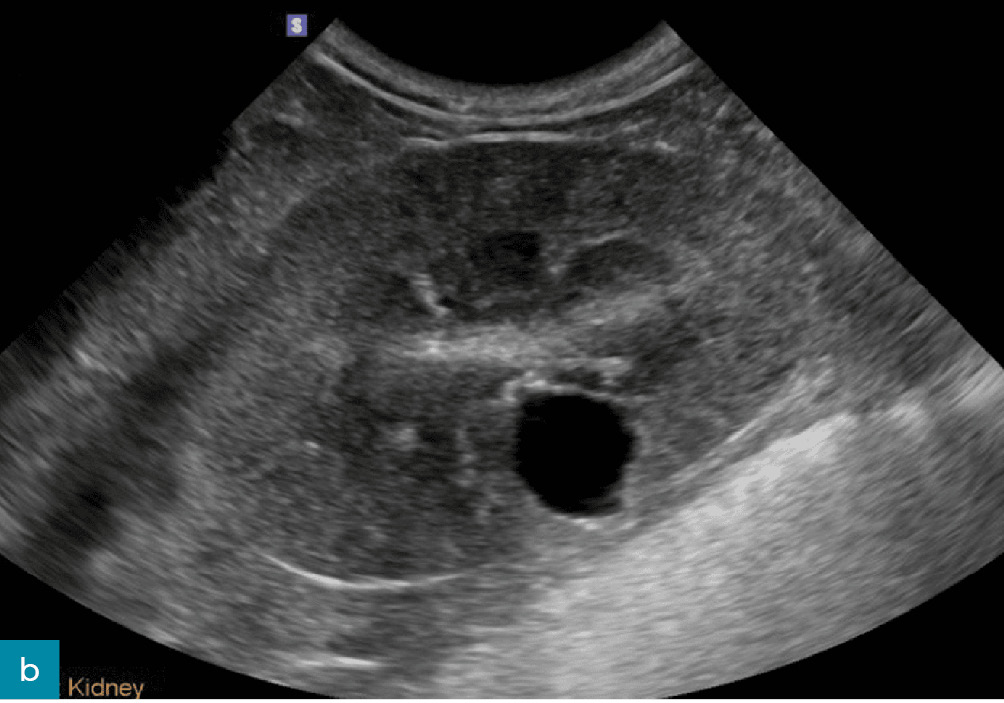

Torbiele nerek

Torbiele nerek (ryc. 12) występują częściej w korze nerkowej i mogą mieć charakter nabyty lub wrodzony. Dlatego też nie stanowią one czułego wskaźnika przewlekłej choroby nerek u psów, jeżeli nie mamy do porównania wcześniej wykonanego badania.8,17 Torbiele nerek są często stwierdzane u psów z przewlekłą chorobą nerek i zazwyczaj nie wpływają istotnie na czynność narządu. Mogą jednak zmieniać kształt nerek i być jednym z czynników powodujących nieregularność ich brzegów.8,12,21

• Medium 2057

• Medium 2094

Ryc. 12. Obraz w projekcji strzałkowej (a) i poprzecznej (b) lewej nerki psa, uzyskany odpowiednio za pomocą głowicy mikrokonweksowej i liniowej. W centrum kory nerkowej widoczna jest dobrze odgraniczona, gładko obramowana, cienkościenna, okrągła, bezechowa torbiel ze wzmocnieniem dalszym. Kora nerkowa wykazuje słabo zdefiniowane hiperechogeniczne prążkowanie oraz zmniejszone zróżnicowanie korowo-rdzeniowe. Łagodna pielektazja (wysokość miedniczki nerkowej < 2 mm) była głównie uznawana za wtórną do diurezy (na przykład fizjologicznej, spowodowanej dożylnym podaniem płynów bądź niewydolnością nerek). Obraz w projekcji strzałkowej dodatkowo wykazuje poprawę rozdzielczości przestrzennej przy użyciu głowic liniowych o wyższej częstotliwości.